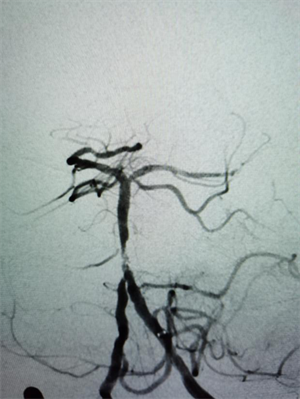

在麻醉科及脑血管介入团队的积极配合下,15:35股动脉穿刺成功,造影发现基底动脉闭塞,经导管抽吸取出血栓一枚,15:56血管再通,复查造影显示基底动脉中下段重度狭窄,后在狭窄段置入血管支架一枚。手术顺利,当晚患者神志转清醒。